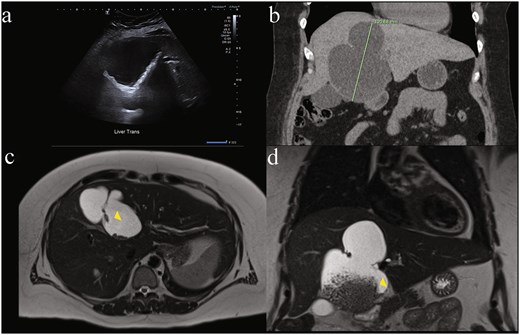

Ultrasound measured a 13 × 17 × 9.5 cm complex cystic lesion in segment IVb of the liver, exhibiting thick septations, wall calcifications with internal matrix echogenicity or debris, without common bile duct (CBD) dilatation (5.3 mm) (Fig. 1a). Subsequent computed tomography (CT) characterized the lesion as a large (9.8 × 6.8 × 12.1 cm) non-enhancing cyst occupying segments IV a/b with internal debris, peripheral calcifications and left hepatic lobe biliary tree dilatation concerning for biliary cystadenoma (Fig. 1b). Magnetic resonance (MR) demonstrated dependent debris with characteristic "hydatid sand" appearance and septations (Fig. 1c and d), without biliary involvement or dilatation. Despite negative hydatid serologies, WHO CE1 and CE2 active stage classification according to WHO informal working groups on Echinococcosis guidelines (constructed for ultrasound) was suggested. Consequently, preoperative albendazole 400 mg twice daily was commenced on the advice of the infectious disease specialists. Tumour markers Alpha-fetoprotein (AFP) and Carcinoembryonic antigen (CEA) were not elevated. Ca 19–9 was not tested.

Diagnostic difficulty represented in single patient imaging series of mucinous cystic neoplasm of the liver (MCN-L). There is wide variation between modalities in same patient: (a) ultrasound of liver demonstrating internal matrix echogenicity or debris, (b) coronal contrast enhanced CT showing non-enhancing cystic lesion 12.1 cm in largest dimension occupying most of segment IV a and b with internal debris, peripheral calcifications and left hepatic lobe biliary tree dilatation reported as concerning for biliary cystadenoma, and magnetic resonance imaging (MRI) T2-weighted. (c) Axial and (d) coronal views showing dependent debris with characteristic ‘hydatid sand’ (yellow arrowhead) appearance and septations concerning for hydatid disease that were later found to be bile stones.